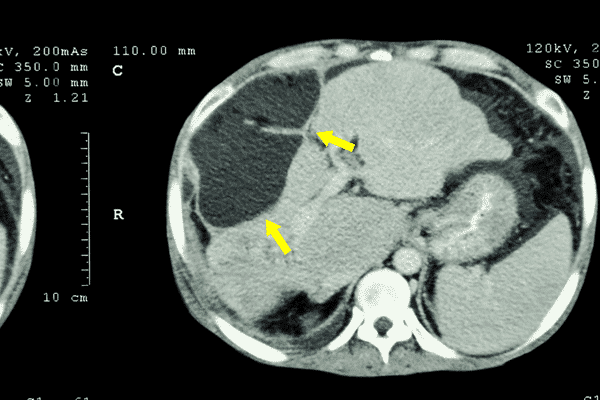

يمكن تشخيص سرطان الكبد باختبارات الموجات فوق الصوتية والتصوير المقطعي والتصوير بالرنين المغناطيسي. تتيح هذه الاختبارات التقاط صور لتجويف البطن والحصول على صورة شاملة. من الممكن أيضًا إجراء اختبار الخزعة ، والذي يتم من خلاله أخذ عينات من الخلايا من منطقة الكبد.